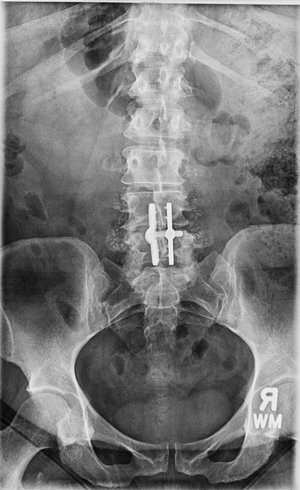

Single-level

L4-5 Laminectomy & Fusion

Lumbar L4-5 Laminectomy & Fusion